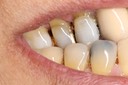

Larry Fujioka #11-12 pre-op

Larry Fujioka #12 pre-op